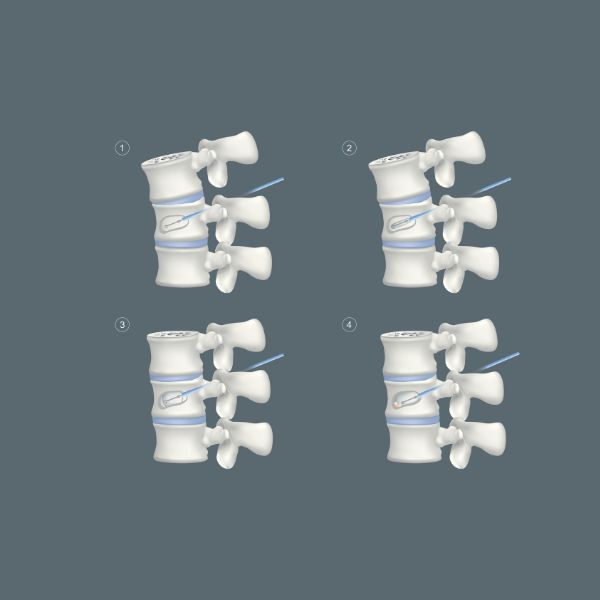

Η κυφοπλαστική είναι μια νεώτερη τεχνική για την αντιμετώπιση των συμπιεστικών καταγμάτων των σπονδύλων πού εφαρμόζεται και αυτή με τοπική αναισθησία και ακτινοσκοπική καθοδήγηση. Το πλεονέκτημά της σε σχέση με τη σπονδυλοπλαστική είναι ότι επιπρόσθετα με την ανακούφιση από τον πόνο, σταθεροποιεί τη σπονδυλική στήλη και αποκαθιστά το ύψος και την παραμόρφωση της. Επίσης η έγχυση του τσιμέντου είναι πιο ελεγχόμενη ελαχιστοποιώντας τις πιθανότητες να διαρρεύσει προς το σπονδυλικό σωλήνα.

Μια κάνουλα εργασίας τοποθετείται στο σώμα του πάσχοντος σπονδύλου δια μέσω του αυχένα, αμφοτερόπλευρα της σπονδυλικής στήλης. Γίνεται τρυπανισμός του οστού και στη συνέχεια τοποθετείται ένα ειδικό μπαλόνι από κάθε μεριά. Τα μπαλόνια αυτά φουσκώνονται με σκιαστική ουσία, ελεγχόμενα με ειδική συσκευή που μετράει την πίεση και παρακολουθούνται ακτινοσκοπικά. Όταν επιτευχθεί η επιθυμητή αποκατάσταση του ύψους και του σχήματος του σπονδυλικού σώματος τα μπαλόνια ξεφουσκώνουν και αποσύρονται. Η κοιλότητα που έχουν δημιουργήσει γεμίζει αμέσως με ακρυλικό τσιμέντο, το οποίο πήζει ταχύτατα και σταθεροποιεί το σπόνδυλο στην κανονική του θέση.

Μερικές ώρες αργότερα ο ασθενής είναι σε θέση να κινητοποιηθεί πλήρως και χωρίς πόνο. (6,11,12,13,14)